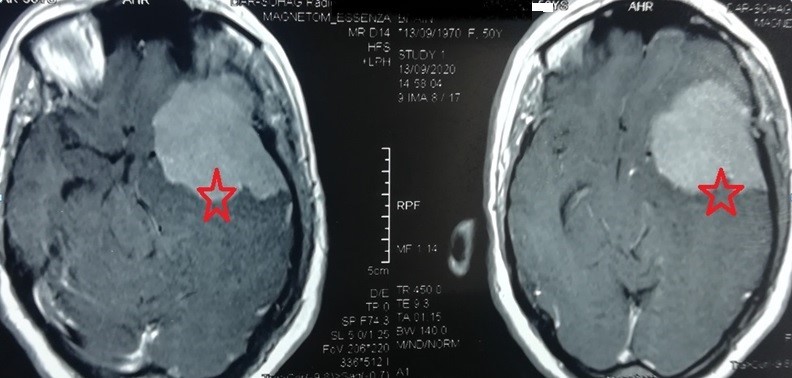

ورم سحائي ضخم بقاع الجمجمة بالجهة اليسري الصدغية

large meningioma at the base of the skull on the left temporal side

A huge meningioma at the base of the skull on the left side, extending into the temporal lobe and part of the frontal lobe, compressing the optic nerve, carotid artery, and left median artery. It clearly compresses all parts of the left hemisphere of the brain. It was completely removed without any significant brain problems, as shown by the radiographs in the follow-up four months after the surgery. The 50-year-old patient was suffering from persistent headaches, seizures and visual impairment. The patient is in very good condition and is going about her life as usual.